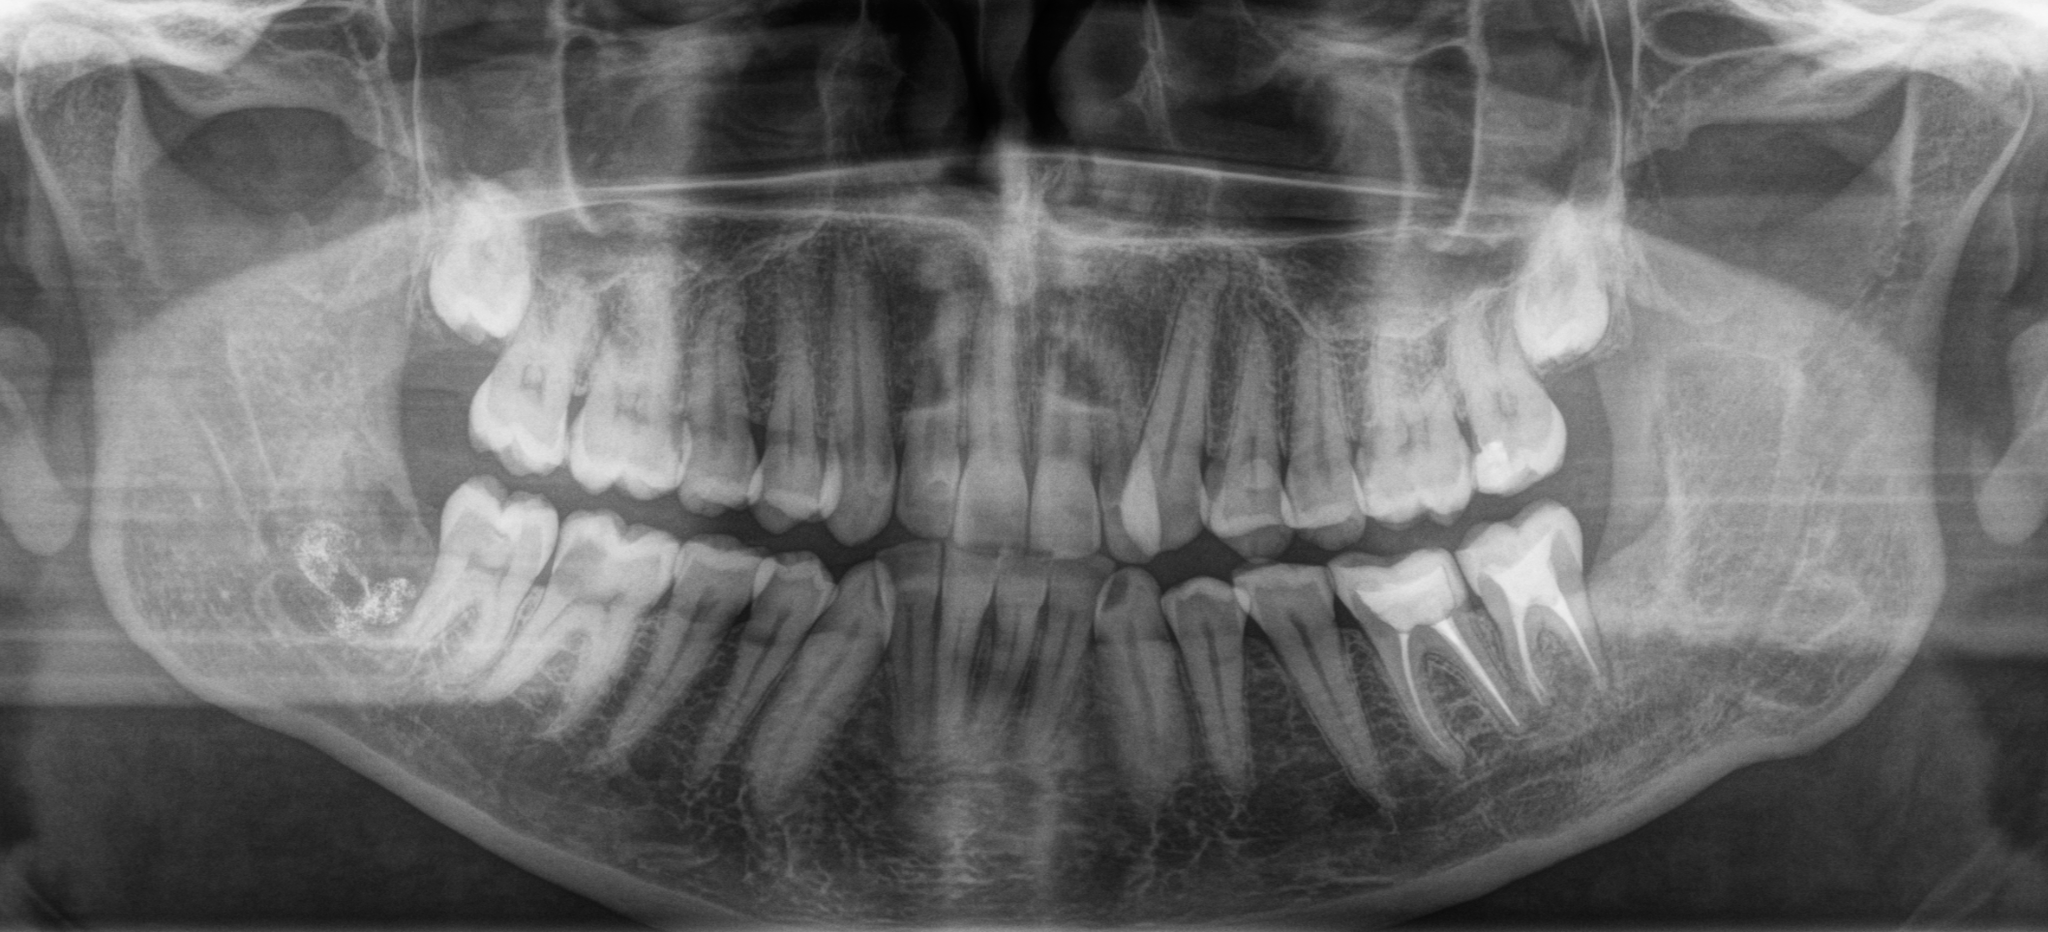

Так вот в один из таких погожих деньков в клинику обратился пациент с жалобой на дискомфорт на нижней челюсти. Ну, видать, зуб мудрости дал о себе знать, думаю я, дело то житейское. Направил на компьютерную томографию, а сам пошел попить чайку с мыслями о том, что без труда, не заморачиваясь, удалю зуб и дело с концом. Размешиваю, значит, сахарок, делаю глоток… Хорошо, думаю, сейчас бы выходной, да на фазенде, а не вот это вот все… Через несколько минут приходит ассистентка с растерянным выражением лица. Ну что, вопрошаю я, пойдем быстренько зуб удалим? Поставил стакан с чаем на стол, уверенный, что успею вернуться до того, как он остынет. Итак, мы с ассистенткой и ее недвусмысленной улыбой пошли в рентгеновский кабинет. И вот, что я увидел на компьютерной томографии:

«Сссука», – мимолетно проскользнуло у меня в голове. Так вот почему лицо ассистентки было таким. В голове крутились мысли: «ведь эта штука росла годами, а раз пациент не обращался к стоматологу, значит, не беспокоила». Вот вам, думаю я, и «не пойду к врачу, пока не заболит».

На нижней челюсти слева у пациента была внушительных размеров фолликулярная киста, которая занимала половину ветви челюсти.

Красным пунктиром я выделил границы этой кисты на срезах компьютерной томографии. Зуб, как вы можете заметить, находится аж у угла челюсти. Если говорить простым языком, то зуб сместился ввиду давления, которое формируется внутри кисты, за счёт чего, кстати, она и увеличивается. Киста достаточно большая, в связи с чем корни 6-го и 7-го зуба были вовлечены в воспалительный процесс. Если сравнить расположение 8-ки с противоположной стороны, то можно заметить, что она располагается намного ближе к 7-му зубу.

С 6-кой все понятно. В нем когда-то были вылечены каналы (белые полоски в корнях зуба – пломбировочный материал), а вот в 7-м зубе такую манипуляцию не проводили. Необходимо убедиться, а живой ли он. В данном случае проводится специальная холодовая проба, которая позволяет понять – живой зуб или нет. Выяснилось, что 7-ка пала смертью храбрых. В таком случае каналы в этом зубе также необходимо пролечить, что и сделали наши великолепные терапевты до удаления.